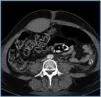

Treatment with methylprednisolone, cyclophosphamide and plasmapheresis (anticoagulation with citrate and replacement initially with albumin and later combined with plasma). Deterioration of renal function persisted with creatinine of 8.4mg/dL and oliguria. Haemodialysis without heparin was begun. After thirteen days the patient complained of pain in the hypogastrium and left iliac fossa following a coughing episode. An abdominal mass and anaemia of four points were apparent. An abdominal CT revealed a haematoma of the left anterior rectus sheath (figure 1). Three concentrates were transfused. A coagulation test including factors was normal except for an Ivy value of ten minutes. Three days later there was new pain in the right iliac fossa, with paralytic ileus and anaemia of three points. A CT revealed a haematoma in both anterior rectus muscles which extended towards the Retzius space and pelvis (figure 2). It pinpointed four concentrations of erythrocytes. The departments of surgery and interventional radiology consulted, deciding on conservative expectant treatment and associating antibiotics (clavulanic amocycillin) as well as parenteral nutrition.

Figure 1.